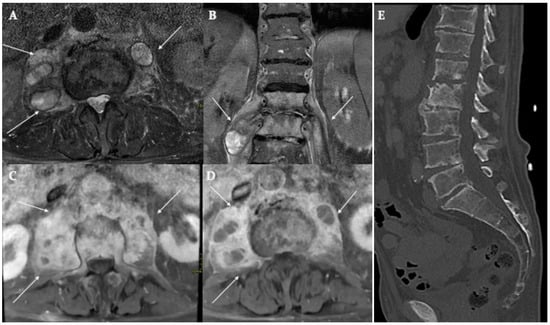

Paraspinal and Iliopsoas Abscess